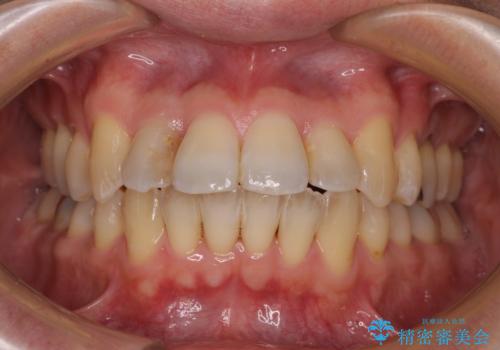

舌の突出癖の影響か、下顎前歯がなかなか整わず、治療期間は予定よりも長期間となりました。

舌突出癖改善のトレーニングの重要性を認識することとなりました。